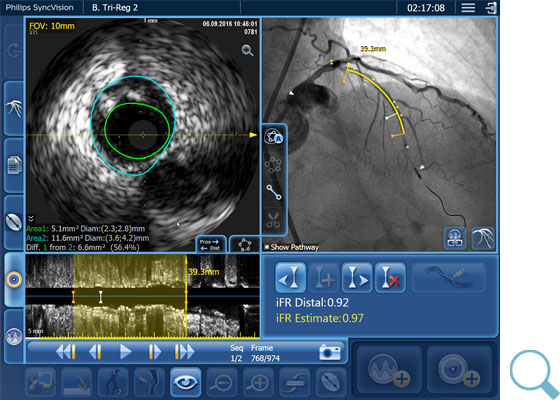

血管造影だけでは、病変の位置を特定するには不十分です。当社製品は、iFR¹,²,³の値を血管造影図にコレジストレーションすることで、高度なPhysiology評価が可能になり、血管のどの位置で虚血を起こしているのか正確に見たうえで、治療戦略を決定することができます。

iFR コレジストレーションでは血管拡張剤が不要で、時間のかかるプルバック装置の操作もなく、憶測ベースでの評価をなくします。

iFR コレジストレーションは手動プルバックにより、ワイヤーを引いた距離の自動校正が行われます。そのため、血管造影図および、圧のトレンドライン上の血管長も把握できます。

「クリック&ドラッグ」の長さ計測により、治療戦略の策定を支援

IVUS および iFR 情報を血管造影図と組み合わせた長さ計測は、ステントがPCIの成功を満たすものであるかどうかの判断を支援します。